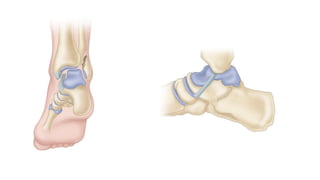

• FUNCTIONAL BIMALLEOLAR FRACTURE

(deltoid ligament tear with fibular fracture)

 Operative (ORIF of lateral malleolus)

 can see significant lateral translation of the talus in this pattern

 not necessary to repair medial deltoid ligament

 only need to explore medially if you are unable to reduce the

mortise